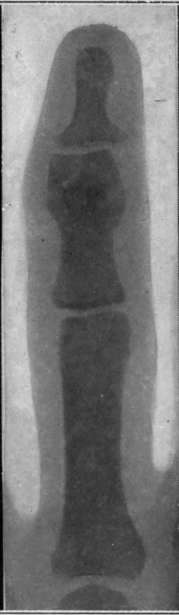

Plate VI.

Fig. I.-- A very exaggerated case of undetected fracture of the finger, showing deformity arising as in Fig. 12. The case came under observation about six months after the injury, as the appearance and character of the swelling around the part suggested tuberculosis.

Fig. II - Fracture of head of phalanx of finger shown by x-rays after two months' treatment for sprain.

Fig. III. - Fracture of base of proximal phalanx of thumb after six months' treatment for sprain. Acute pain was the symptom complained of, which rendered the hand quite useless. Removal of the ununited fragment effected a cure.